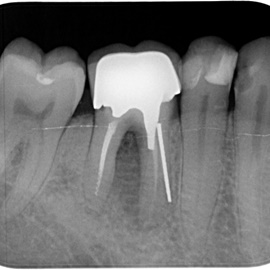

Odbudowa lewego dolnego trzonowca.

Odbudowa prawego dolnego trzonowca.

Odbudowa kości, dziąsła, implantacja, korony protetyczne, dwa prawe dolne trzonowce.